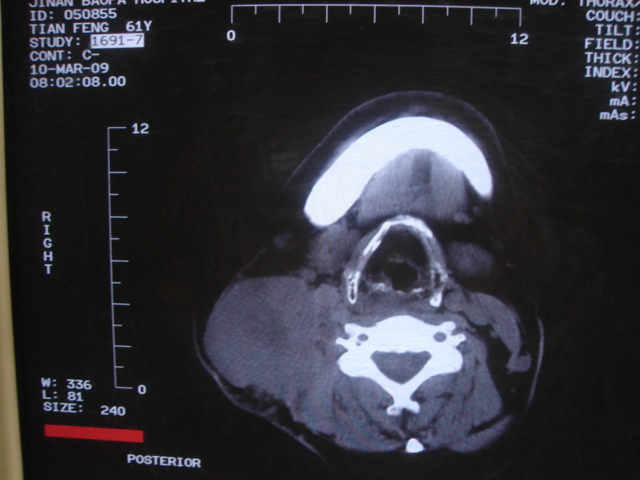

患者 男 61  甲状腺ca术后7年 颈部淋巴结转移

声门下区表面不光整,增厚呈局限性突起,未见局部浸润.

考虑----颈部淋巴结转移,不排除---喉乳头状瘤可能.

颈部多个淋巴结增大,结合甲状腺ca术后7年病史考虑转移。

另声门区不规则突起,建议喉镜检查!

右侧颈部淋巴结转移,右声带乳头突起,乳头状瘤可能性大。

1)右侧颈部淋巴结转移瘤。2)右侧声带新生物,性质待定;建议喉镜检查(活检)。

结合病史符合甲状腺ca术后颈部淋巴结转移